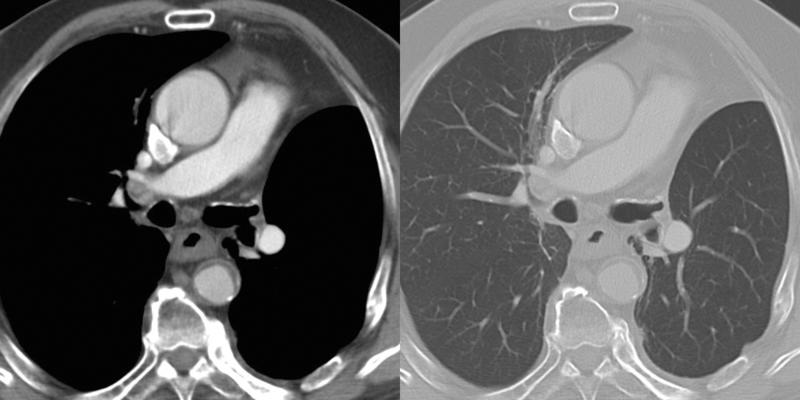

Lobar Collapse

LUL Collapse

LULobectomy ex 2